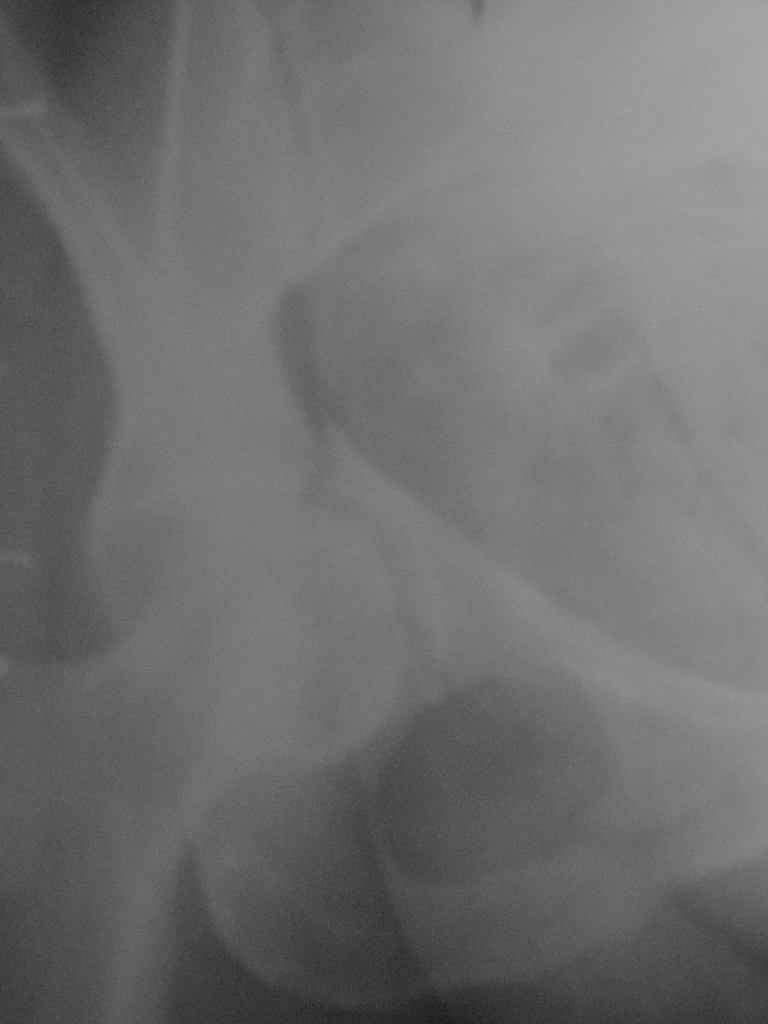

Женщина,58 лет, после ДТП 6 суток. Первично повреждение расценено как переломы ветвей лонной кости. После подтверждения повреждения вертлужной впадины,как чаще всего случается, вопрос встал о тактике. БОльшинство за консерватиное лечение.К сожалению кт у нас "во время" сломался. Прилагаю стандартные снимки вертлужки. У меня следующие вопросы к коллегам:1. Правильно ли рассценивать это повреждение как Т-образный перелом вертлужнй впадины?2. Можно ли добиться анатомической репозиции поверхности вертлужной впадины скелетным вытяжением в данном случае, если нет, что будет этому препятствовать?3. Если смещение останется таким как сейчас, через какое время появится необходимость эндопротезирования (по вашему опыту)?Спасибо.

Уважаемый Коваленко А.Н., снимки плохого качества и нет уверенности, что задняя колонна сломана (смещена). Если кт нет - везите больную в рентгенкабинет (палатником качественные снимки снимки не получатся) и сделайте обзорный снимок таза, Judet и может быть inlet, хуже вы ей не сделаете.